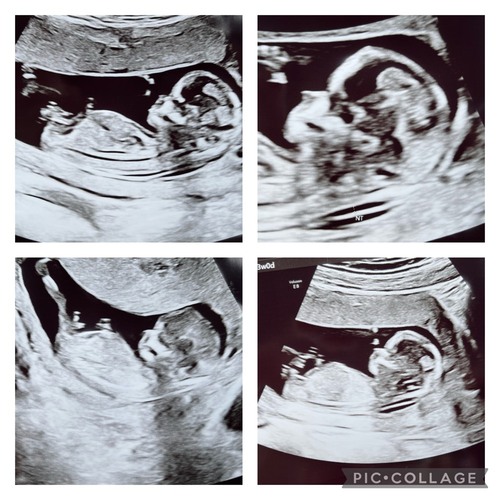

Hier heb ik nog een paar foto’s erbij maar denk dat die ene die ik eerder al stuurde het meest duidelijk is. Ik ben benieuwd wat jullie denken!

Hier heb ik nog een paar foto’s erbij maar denk dat die ene die ik eerder a ...

💗